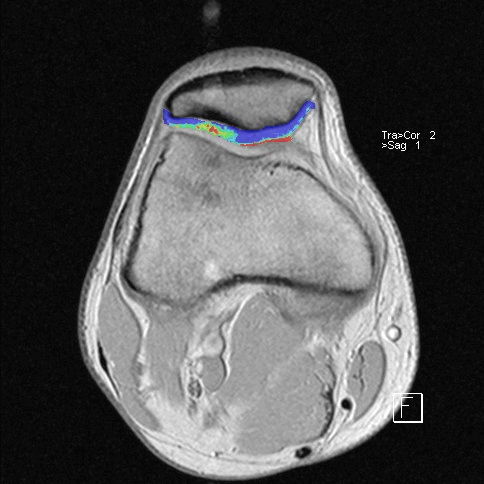

Дистрофические изменения суставного хряща надколенника (с использованием опции «картирования хряща»)